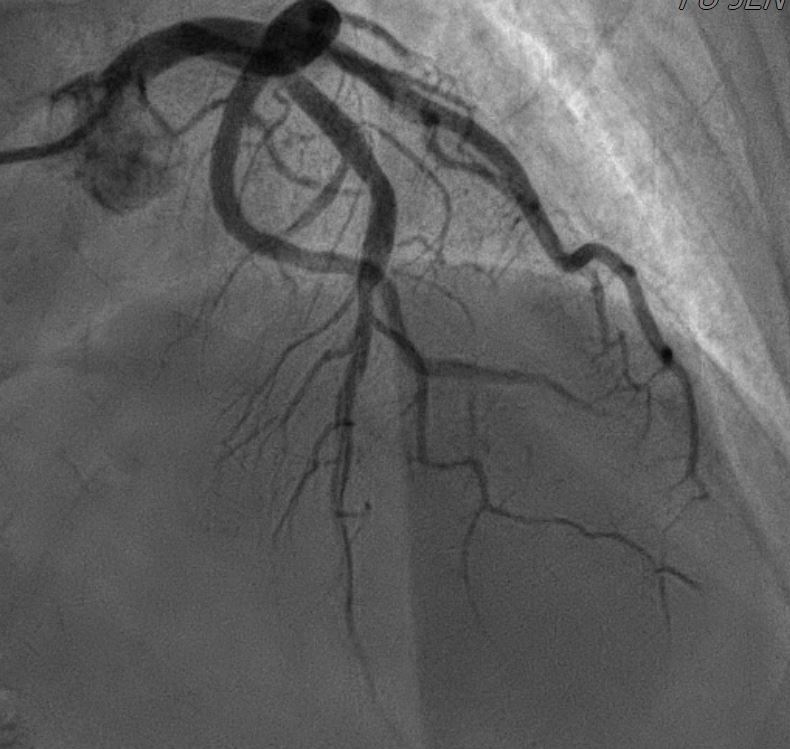

In the STEMI episode, in Dec, 2022, the LCX and RCA were patent. There were multiple odd stenotic lesions with in mid LAD, with some haziness suggested limited contrast filing. Six days after PCI, there was dissection flap, extending beyond previous angioplasty, with limited flow in LAD, compatible with the unstable ECG changes. In the NSTEMI episode, in Dec, 2022, the LAD was stationary without restenosis. But the RCA for new log lesion at segment 2 to segment 3.

1st PCI for STEMI 1. The odd LAD lesion was checked by IVUS,revealing coronary dissection in mid LAD. 2. Angioplasty was performed with a 2.75*10mm Wolverine cutting balloon up to 8A10¡±, with fair LAD flow. --2nd PCI for recheck and unstable ECG findings 1. For dissection flap extending to distal LAD, wiring with a Sion wire was performed carefully. 2. Check IVUS to confirm true-lumen wiring and the extension of the dissection. Intimal flap and large burden of sub-intimal hematoma were noted. 3. Angioplasty with a 2.0*20mm balloon catheter, but with poor distal flow. 4. Long stenting to mid-to-distal LAD according to IVUS findings, with Onyx 2.0*26mm and Onyx 2.5*30mm 5. Angioplasty with a 1.5*20mm balloon catheter for distal run-off, 4A10¡± 6. Post-stenting dilatation with a 2.5*10mm balloon catheter, 4A10", low pressure considering the sub-intimal hematoma 7. Check final IVUS: The stents were well apposed. The proximal sub-intimal hematoma was not fully covered due to the vessel-size discrepancy. 8. The final flow was fair --3rd PCI for NSTEMI 1. For the un-reasonable rapid progression of the RCA lesion, I checked IVUS and coronary dissection was noted again. 2. No PCI was performed thereafter due to acceptable blood flow. --4th cath half years later The LAD was stationary and the RCA lesion was totally resolved.